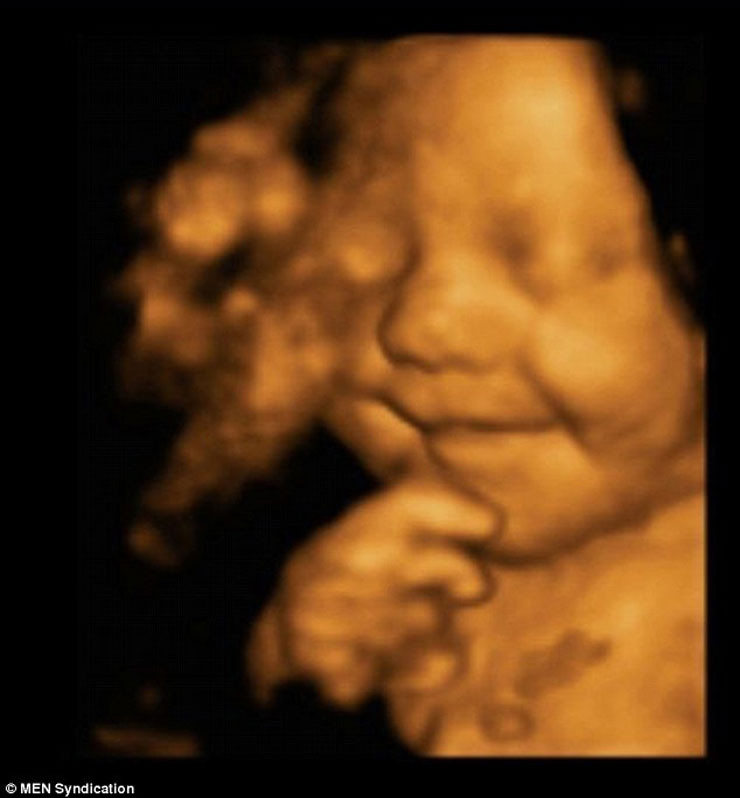

Ένα αγέννητο μωρό εμφανίζεται να… περνάει ευχάριστα και να γελάει μέσα στην κοιλιά της μητέρας του! Οι σχετικές φωτογραφίες που δημοσίευσε η Daily Mail δημιουργήθηκαν με τεχνολογία 4D η οποία είναι πλέον αρκετά δημοφιλής και αρχίζει να κερδίζει έδαφος συγκριτικά με το κοινό υπερηχογράφημα.

Oι μελλοντικοί γονείς δήλωσαν έκπληκτοι όταν είδαν τον γιο τους να τους χαμογελά, μέσα από την κοιλιά της μαμάς, κατά τη διάρκεια της 31ης εβδομάδας κύησης! Οι εικόνες είναι απλά… μαγικές: